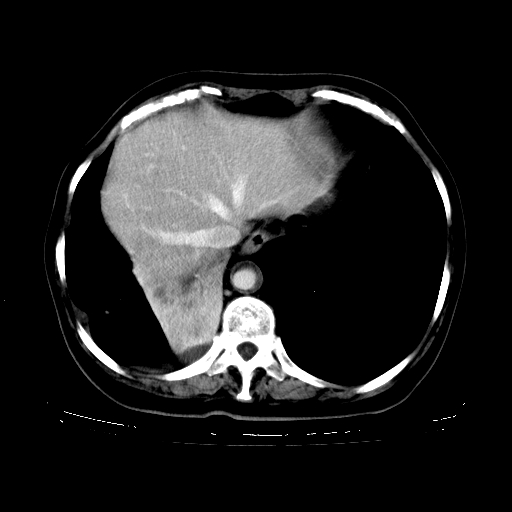

1、右肺占位,考虑周围型ca 。

2、右下肺软组织密度肿块影,考虑肺隔离征。

3、两肺肺结核(右肺下叶背段及左肺)。

4、主动脉夹层。

5、右侧少量胸腔积液。